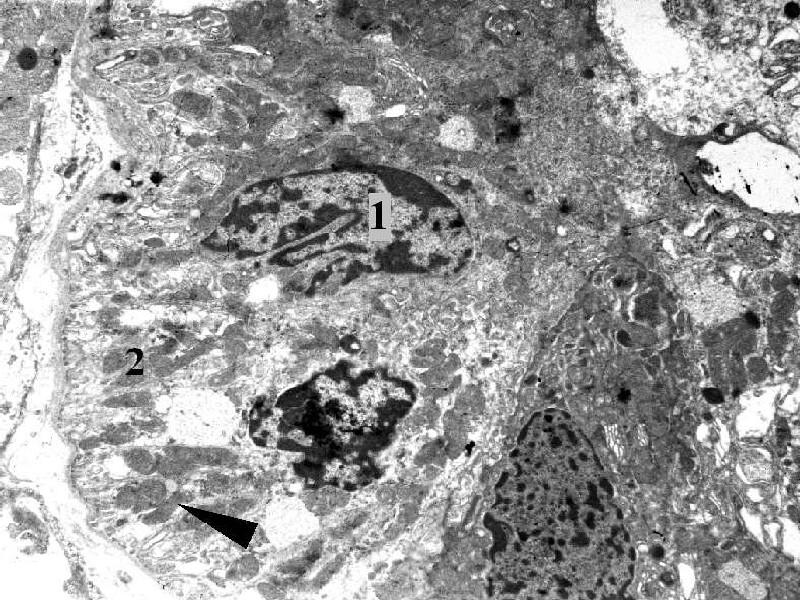

Epitel proximálního tubulu v TEM: jádro (1), bazální labyrint (2) a mitochondrie (šipka).